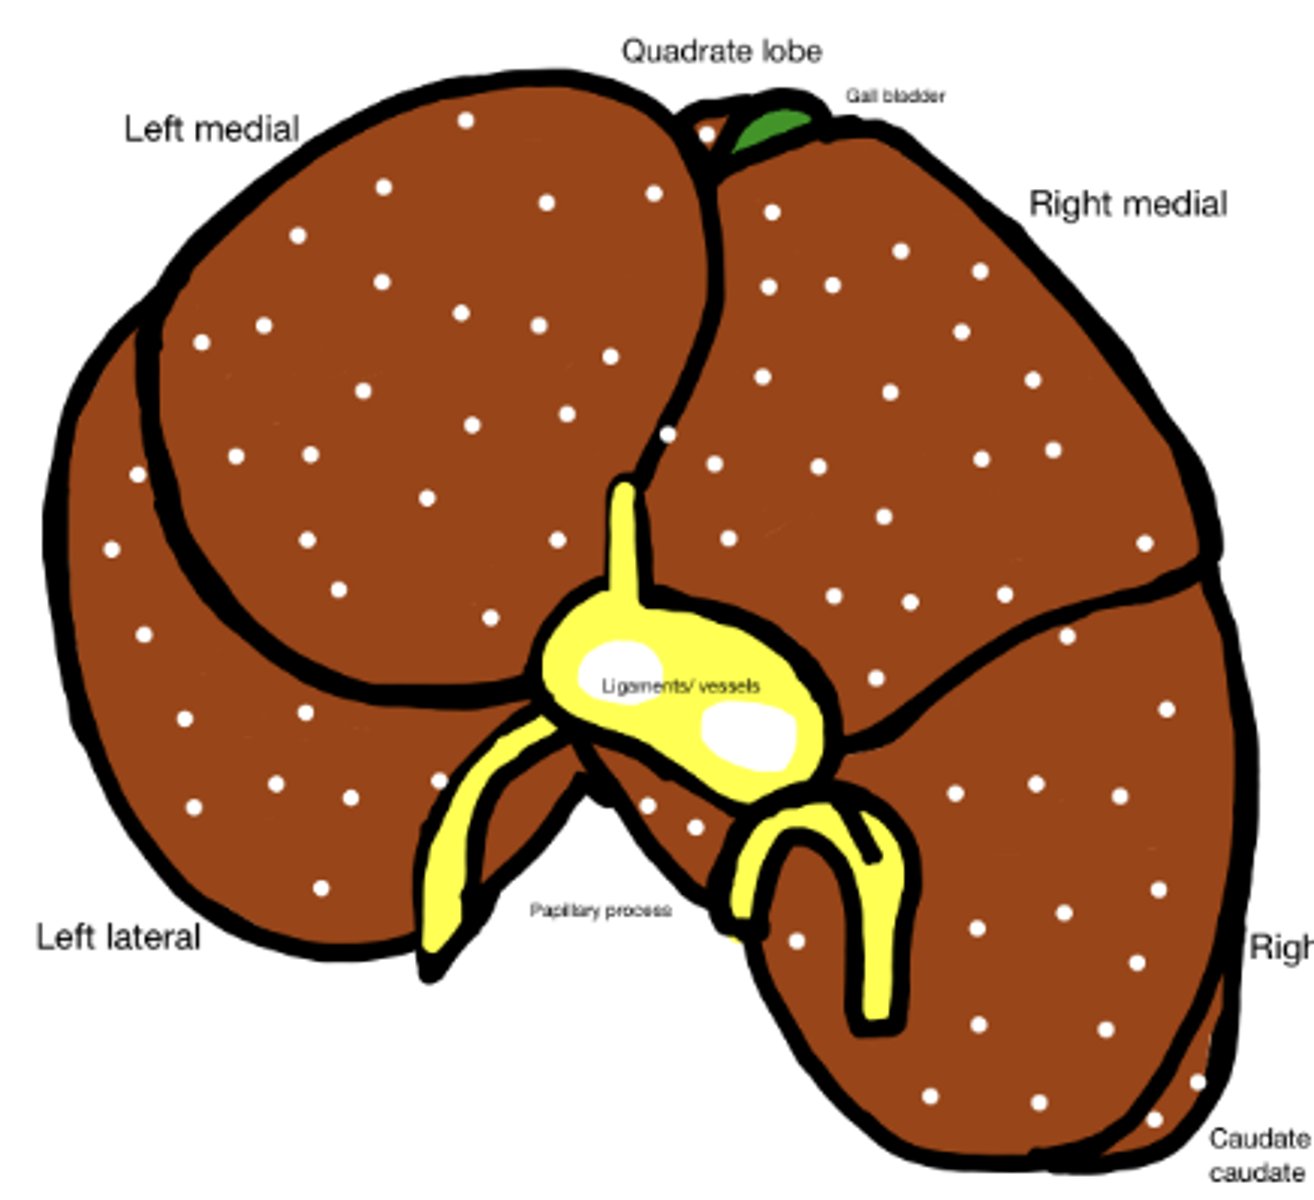

Cirrhosis caused by long term exposure to toxic substances

What has caused this gross appearance of this dog liver